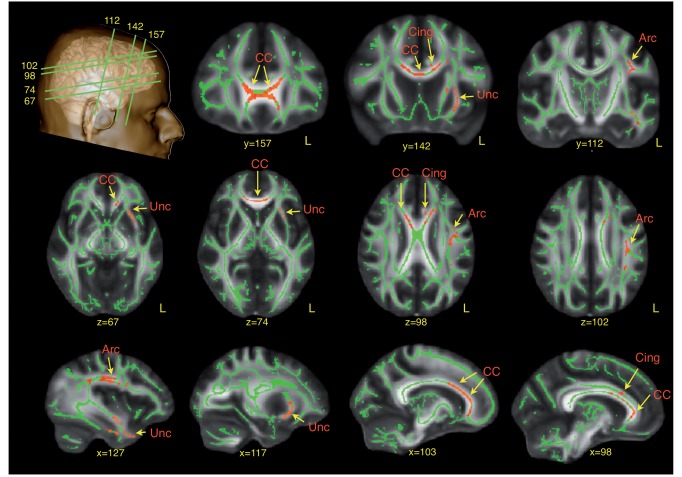

Compared to controls, the ASD group had significantly (corrected for multiple comparisons) lower fractional anisotropy in the left arcuate fasciculus (P = 0.026), external capsule (P = 0.046), anterior (P = 0.044) and posterior (P = 0.032) cingulum, and anterior corpus callosum (P = 0.015). There were no increases in fractional anisotropy in the ASD group compared to controls (Fig. 1).

Figure 1.

TBSS analysis of differences in fractional anisotropy between ASD subjects and neurotypical controls. Red regions indicate reduced fractional anisotropy values in ASD. Arc = arcuate fasciculus; CC = corpus callosum; Cing = cingulum; Unc = uncinate fasciculus.